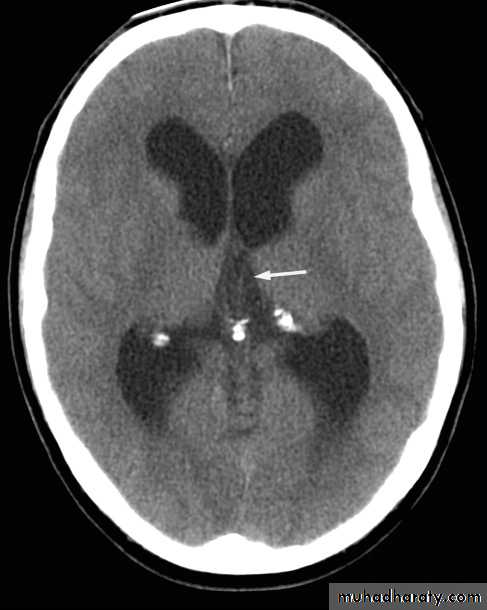

Mass effect

• The lateral ventricles should be examined to see if they are displaced or compressed.• Shift of midline structures, such as the septum pellucidum , the third ventricle, or the pineal, is a common finding with intracranial masses.

Enlargement of ventricles

There are two basic mechanisms which cause the cerebral ventricles to enlarge:• Obstruction to the CSF pathway, either within the ventricular system (non-communicating hydrocephalus) or over the surface of the brain (communicating hydrocephalus)

• Secondary to atrophy of brain tissue